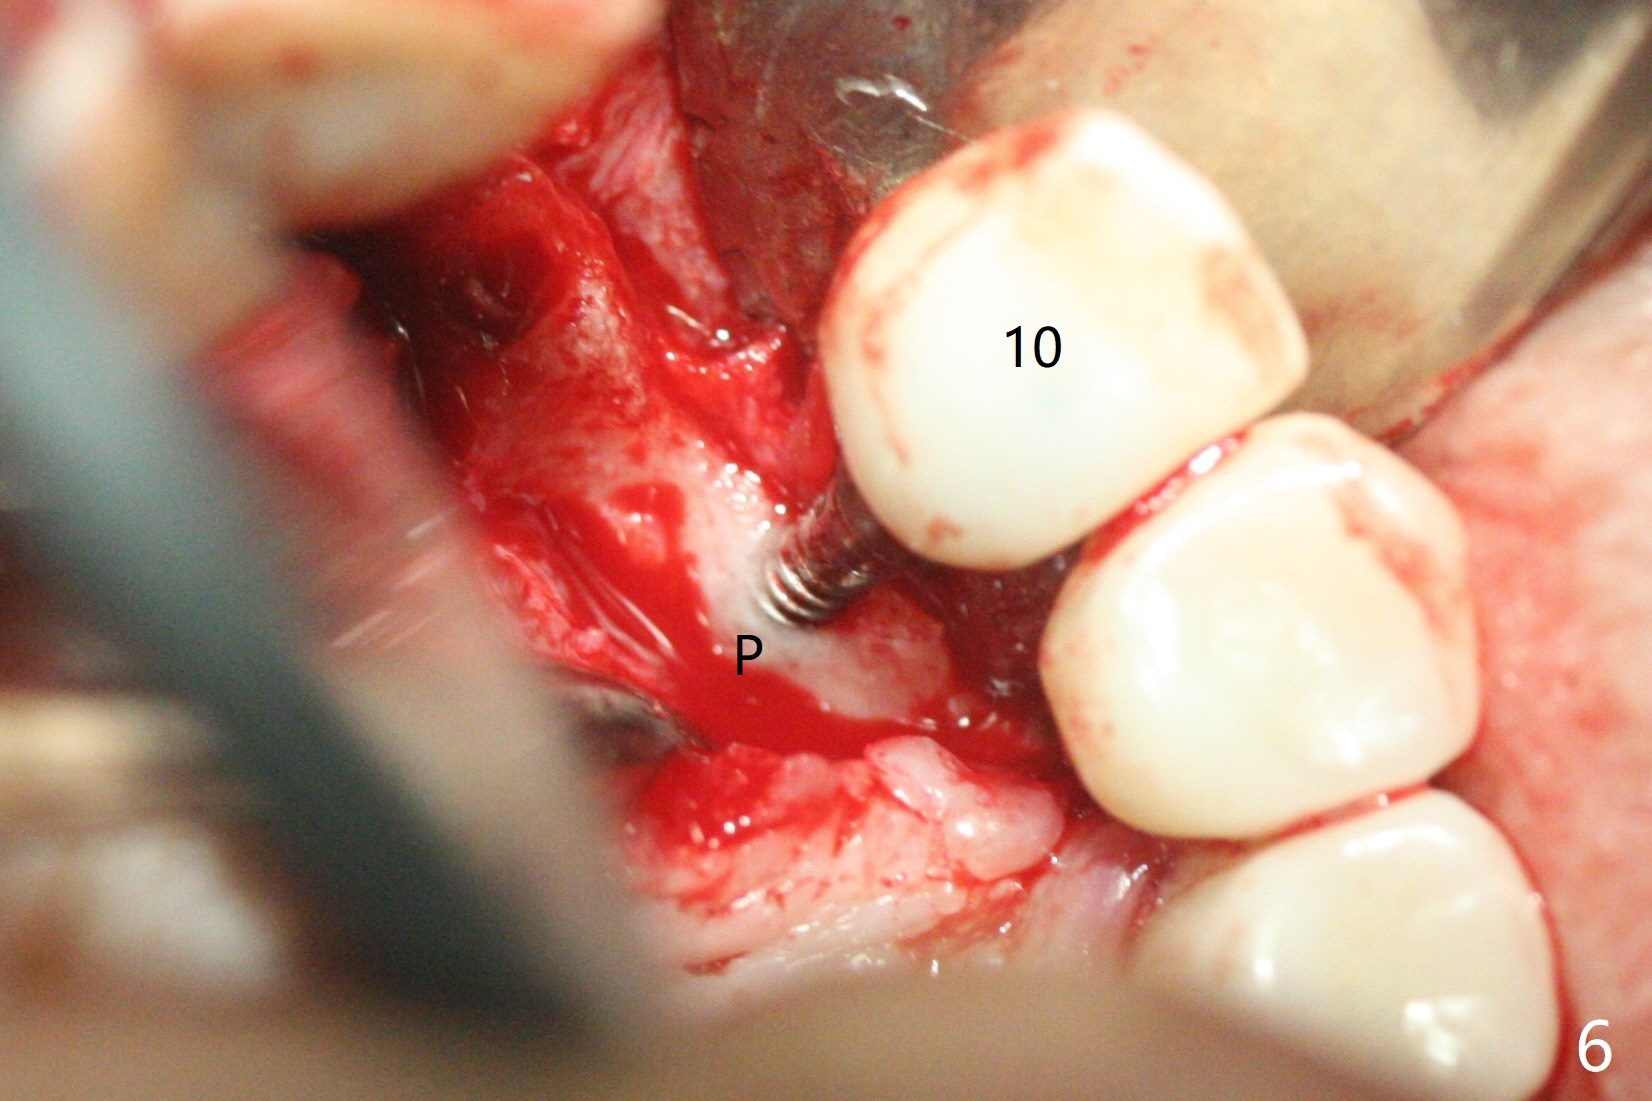

The implant access at #9 closes 1 week post implant fracture (Fig.1,4). There is mild gingival erythema at #10 (Fig.2,3 ^). There is bone around the fractured implant, which is palatally placed (Fig.5). The 2 mm implant is removed using 2/3 mm trephine bur. In spite of moving the osteotomy buccally, a 4.5x4 mm, 15 degree A-type angled abutment is installed for an immediate provisional following placement of a 3.5x10 mm implant (Fig.7, 25 Ncm). Sticky bone is placed (Fig.7 *) palatal to the implants at #9 and 10 (with thread exposure, Fig.6). While the majority of periodontal dressing remains in place (Fig.9,10), the suture in the exposed area appears to hold the papilla in place (Fig.8 <). Herpetic infection develops in the palate (Fig.9). Two months later, the gingiva at #10 is healthy; it appears that the implant threads are covered by bone graft. The immediate provisional (fabricated before suture) keeps the gingiva in an ideal position for impression of final restoration. It appears that the access hole is in a right area for screw retained restoration. The gingival cuff is healthy immediate pre-cementation, 4 months postop (Fig.12,13). The lab does not make access hole for the final crown (Fig.14). The implant remains subcrestal 4 months postop (Fig.15). Since the shade of the crown is off, the abutment remains un-torqued and the crown is cemented with temp bond. The implant threads at #10 seem to be covered by bone graft 4 months postop (Fig.16).